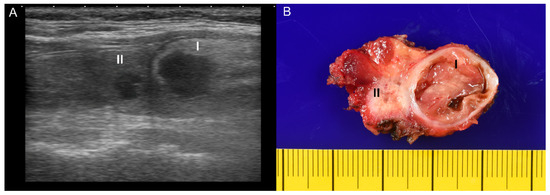

A 51-year-old female had a medical history of diabetes mellitus type 2 and hypertension under regular medical treatment for more than ten years. She complained of anterior neck enlargement and discomfort for three months. The physical examination showed non-tender, soft, elastic nodularity at the central neck. Ultrasound of the thyroid revealed a total of five hypoechoic nodules in bilateral lobes. Of those, the two largest nodules were in the right lobe, heterogeneous and hypoechoic: (I) well-defined, 2.3 × 1.9 × 1.4 cm, and (II) ill-defined, mildly calcified, 1.0 × 1.0 × 0.6 cm (Figure 1A). An ultrasound-guided FNA was performed on the ill-defined nodule II. The liquid-based cytology showed sheets and clusters of thyroid epithelial cells bearing irregular nuclei, nuclear grooves, and intranuclear cytoplasmic inclusions, which were suspicious for PTC (Figure 2A,B). The patient subsequently underwent radical thyroidectomy and unilateral right neck lymph node dissection. Intraoperative consultation confirmed the nodule II was malignant.

In the gross examination (Figure 1B), the right lobe of the thyroid gland revealed two nodules (the larger cystic nodule I: 2.0 × 1.5 × 1.3 cm, and the smaller fibrous nodule II: 0.7 × 0.6 × 0.6 cm), corresponding to the nodules identified on the ultrasound imaging (Figure 1A). On microscopic examination, the nodule I was identified as thyrolipoma containing a variable proportion of mature adipocytes and bland-looking thyroid follicles, which were positive for TTF-1 and negative for BRAF upon immunohistochemistry staining (Figure 3A–D). The nodule II was an unencapsulated classical BRAF-positive PTC (Figure 4A–D). No perineural or lymphovascular invasion was identified, and no extrathyroidal expansion was seen. The left thyroid showed multinodular goiter, and all dissected lymph nodes were negative for malignancy. The patient recovered well and had no recurrence within nine months after surgery.

Figure 1. (A) The ultrasound examination of both thyroid nodules, referred to as the nodule I (2.3 × 1.9 × 1.4 cm) and the nodule II (1.0 × 1.0 × 0.6 cm), showed hypoechoic and heterogeneous. (B) The gross image of the right thyroid from thyroidectomy revealed one well-defined, encapsulated cystic nodule measuring 2.0 × 1.5 × 1.3 cm (I) and one ill-defined, white fibrous nodule measuring 0.7 × 0.6 × 0.6 cm (II).